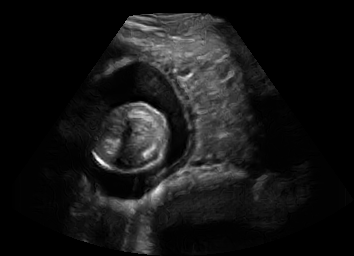

Discussion. Note that, despite both being fetal images, the simulated and the real images have substantially different anatomical contents, which makes the translation task extremely challenging. Nevertheless, our proposed framework is able to generate images with appearance strikingly close to real images, with far superior realism than its competitors. Besides sim-to-real translation, given its multi-domain conditional nature, our proposed framework without any further training can also translate images between the other domains, e.g. seg-to-real or seg-to-sim, with examples presented in Fig. 5.